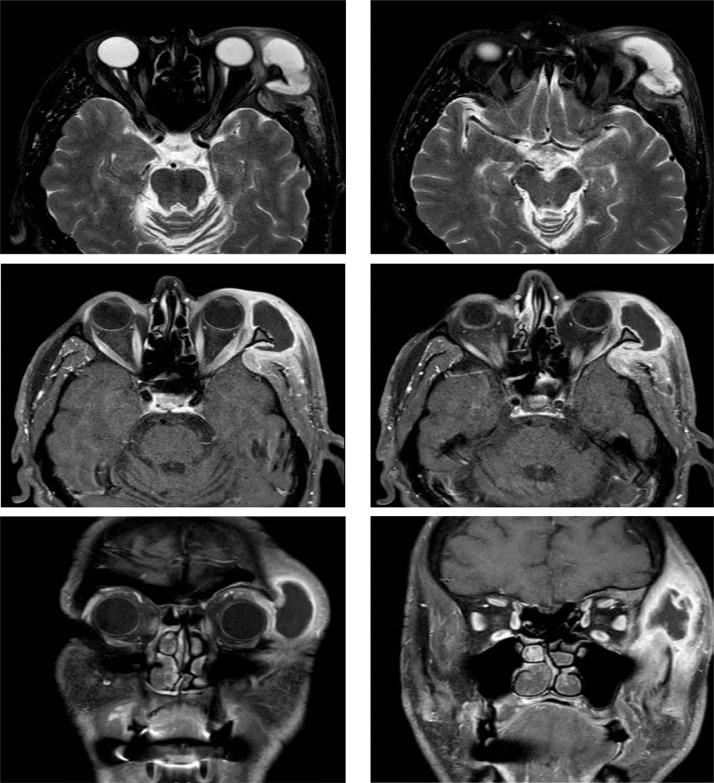

Various infective complications can be seen after a dental procedure. They are rarely resistant to standard therapy. In the case we present, a case of preseptal cellulitis caused by pseudomonas oryzihabitans after tooth extraction in a male patient who did not have any underlying cause. As in our case, evaluation of the cases resistant to standard treatment in terms of drainage and multidisciplinary management of culture results together with infectious diseases will increase the treatment success rate.